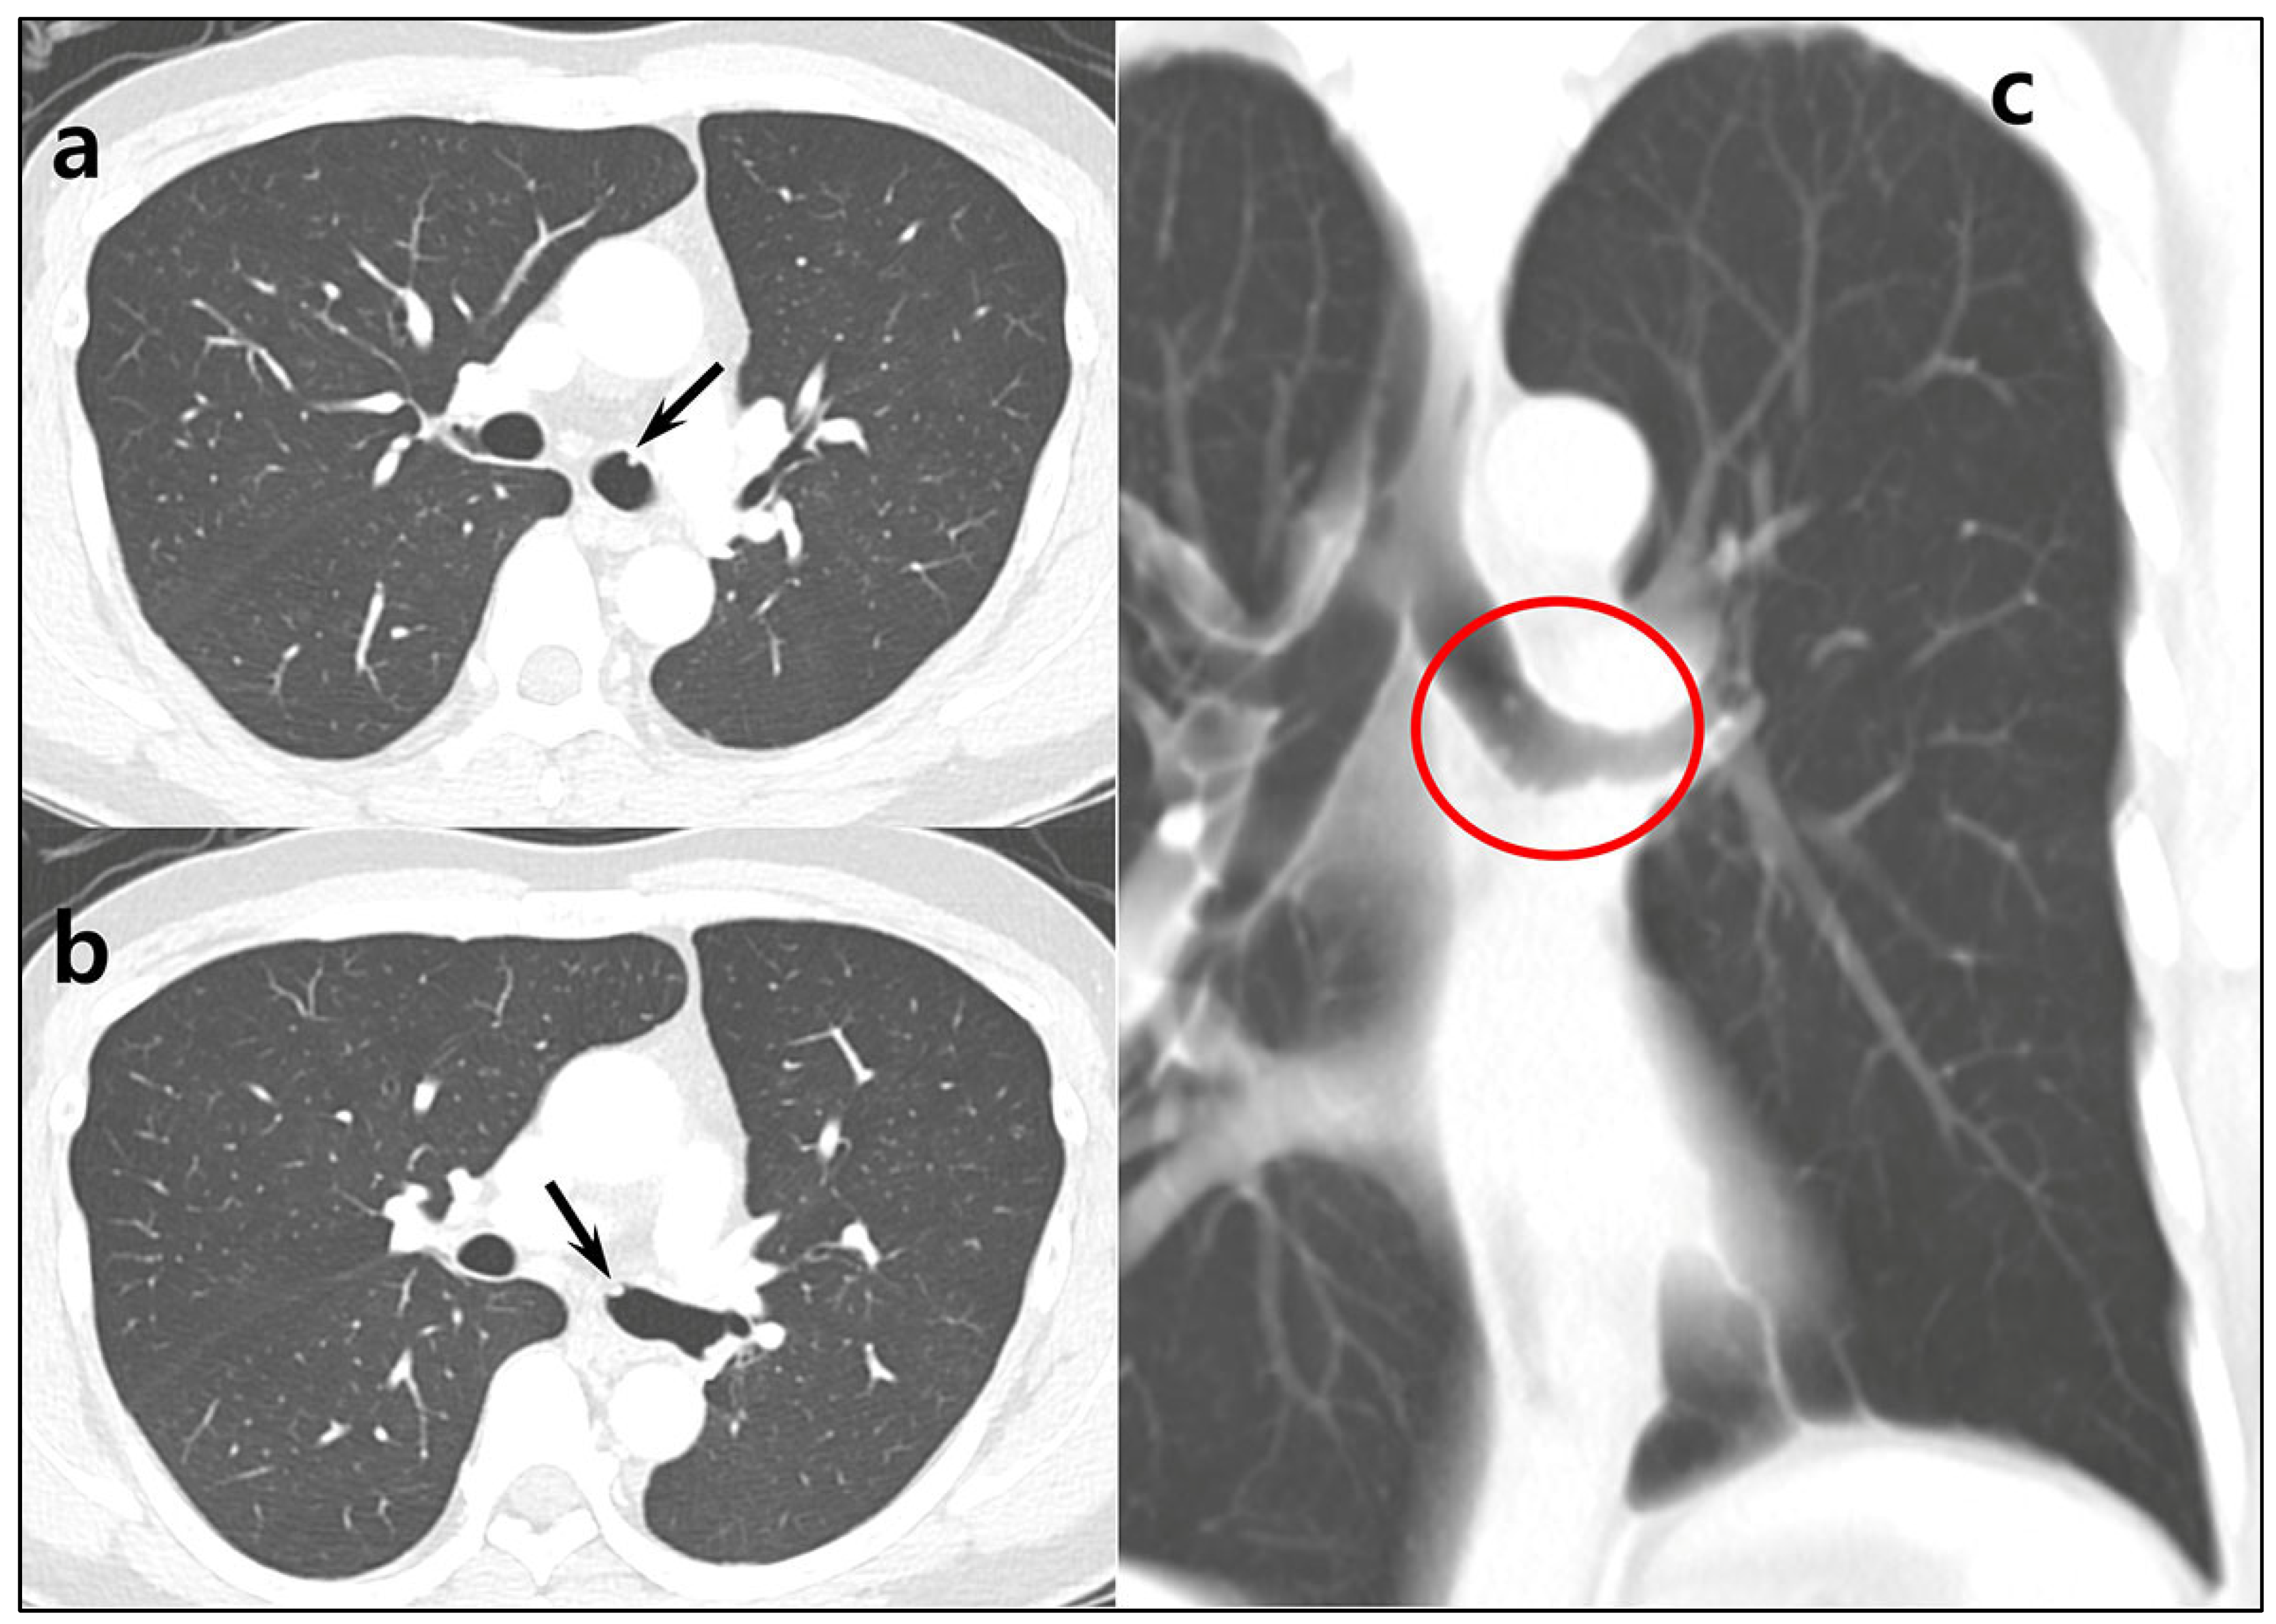

Central Airway Carcinoid Tumorlets Following Resection of a Typical Carcinoid Tumor

Bae, K.; Jeon, K.N.; Heo, I.R.; An, H.J.; Song, D.H. Central Airway Carcinoid Tumorlets Following Resection of a Typical Carcinoid Tumor. Diagnostics 2025, 15, 1651. https://doi.org/10.3390/diagnostics15131651